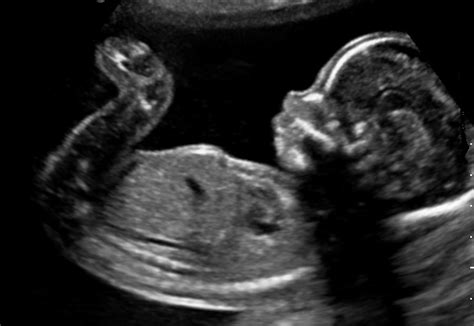

Il bambino, che misura circa 28-30 cm e pesa intorno ai 530 grammi, sta diventando sempre più attivo. I suoi muscoli, tendini e articolazioni sono in fase di sviluppo, permettendogli di esercitarsi e affinare i sensi. Questa attività si traduce in una gamma di movimenti, dai calci e spinte più distinti al singhiozzo ritmico, fino a rotazioni e cambi di posizione.

Il bambino continua il suo rapido sviluppo. Nei polmoni inizia a formarsi il surfattante, una sostanza essenziale per il mantenimento degli alveoli aperti dopo la nascita. L'ecografia può ora visualizzare le camere cardiache e i principali vasi sanguigni. Le orecchie sono pienamente funzionanti, e il bambino può reagire a rumori forti e improvvisi. Le ossa si stanno indurendo, rendendo importante un adeguato apporto di calcio nella dieta materna.